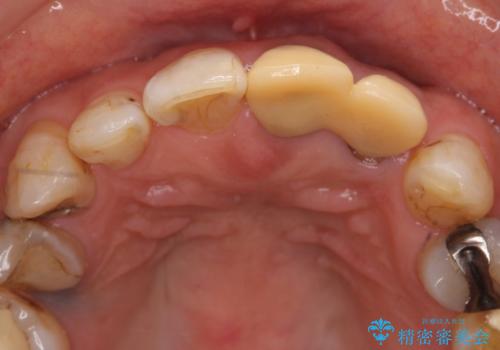

オールセラミッククラウン 前歯のブリッジ 気になる見た目の改善

- 左側の前歯の見た目が気になるといらっしゃった方の症例です。

左上1、2番目の歯は仮歯の状態だったので外して状態を確認したところ、左上2は垂直的な歯根破折を認めたため抜歯となりました。左上1は再根管治療を行いました。

左上2抜歯後、骨および歯肉の回復を待ち、オールセラミッククラウンのブリッジによる欠損補綴を行いました。